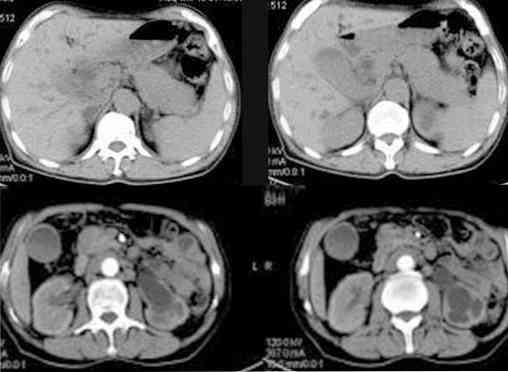

КТ ретроперитонеального фиброза: Изображения и диагностика